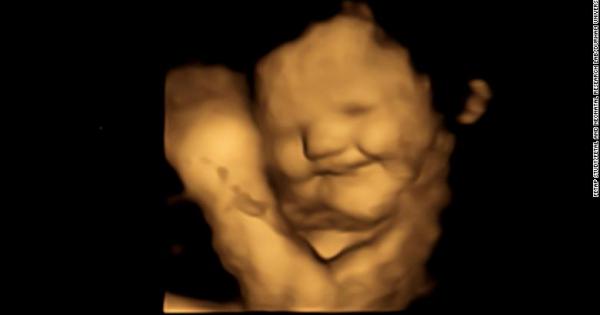

Снимки на фетуси в утробата показват че те се усмихват

...... че повечето от бебетата, изложени на зеле, изглеждат сякаш правят гримаса, докато изложените на морков се усмихват. В контролната група не е имало такива реакции.

...... повечето от бебетата, изложени на зеле, изглеждат сякаш правят гримаса, докато изложените на морков се усмихват. В контролната група не е имало такива реакции.